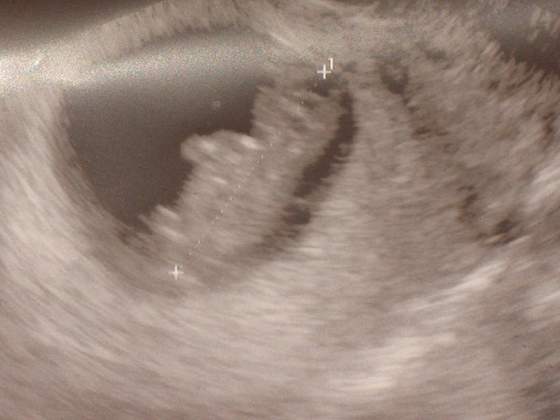

Piekne te wasze dzieciaczki, a jak wy się nimi chwalicie to i ja:tak:

Oto zdjęcie z środowego USG, Michaś, no ewentualnie Hania lub Emilka ma na nim 6,5 cm

Załączniki

• dzidzia1.jpg

dzidzia1.jpg

13,7 KB · Wyświetleń: 160